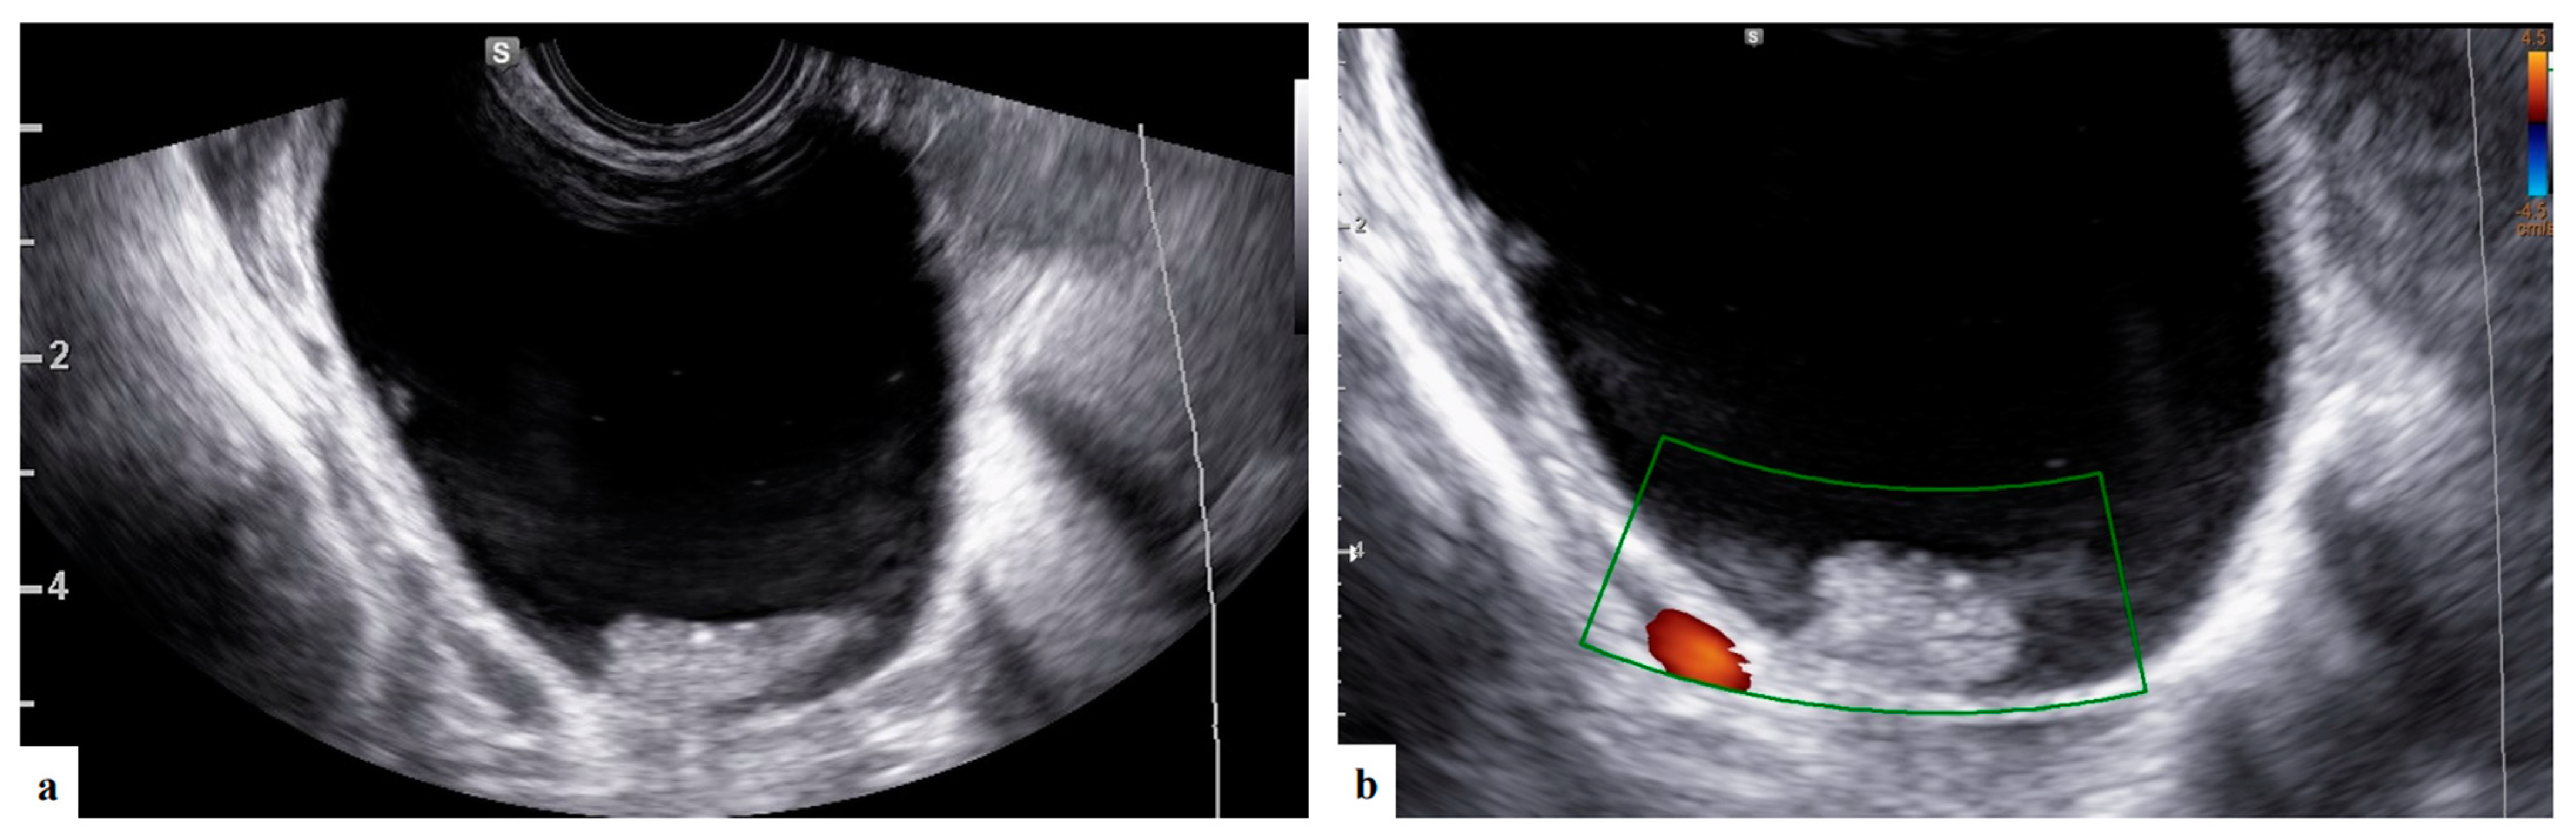

- Bruno, M.; Capanna, G.; Di Florio, C.; Sollima, L.; Guido, M.; Ludovisi, M. Sonographic characteristics of ovarian Leydig cell tumor. Ultrasound Obstet Gynecol. 2023, 62, 441–442. [Google Scholar] [CrossRef]

- Moro, F.; Mascilini, F.; Pasciuto, T.; Leombroni, M.; Li Destri, M.; De Blasis, I.; Garofalo, S.; Scambia, G.; Testa, A.C. Ultrasound features and clinical outcome of patients with malignant ovarian masses diagnosed during pregnancy: Experience of a gynecological oncology ultrasound center. Int. J. Gynecol. Cancer 2019, 29, 1182–1194. [Google Scholar] [CrossRef]